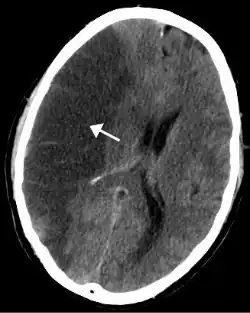

A isquemia em uma parte do cérebro leva ao acidente vascular cerebral (AVC), conhecido como "trombose" (embora nem sempre seja causada por trombos, pode ser também por estenose (estreitamento e/ou bloqueio de uma artéria). Nos membros pode causar gangrena e necessitar amputação. No pulmão pode levar a embolia pulmonar. No intestino é chamada de isquemia mesentérica e pode causar inflamação grave (colite isquêmica). Na pele resulta em descoloração, deixando a pele roxa ou azulada.